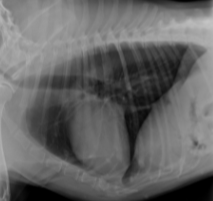

What sign is this?

Bowlegged Cowboy Sign - L. atrial enlargement